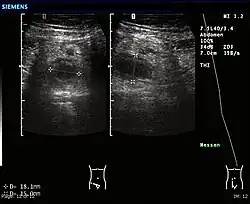

• Ultraschalluntersuchung des Bauchraumes (Kokardenformation, tubuläre Struktur, Abszess, Ausschluss anderer Erkrankungen): Als spezifisches Zeichen für eine Appendizitis gilt ein maximaler Außendurchmesser der Appendix von mehr als 6 oder 7 mm,[10] wobei ein größerer Durchmesser spezifischer ist. Die entzündete Appendix ist zumindest teilweise rund im transversen Schnittbild und nicht kompressibel. Ein Appendikolith ist ebenfalls spezifisch für eine Appendizitis, unabhängig vom maximalen Außendurchmesser der Appendix.[11] Sekundäre Zeichen der Appendizitis sind eine Wanddicke von mehr als 3 mm, ein Halo wegen eines Ödems und vermehrt ödematöses mesenterisches Fett.[12]